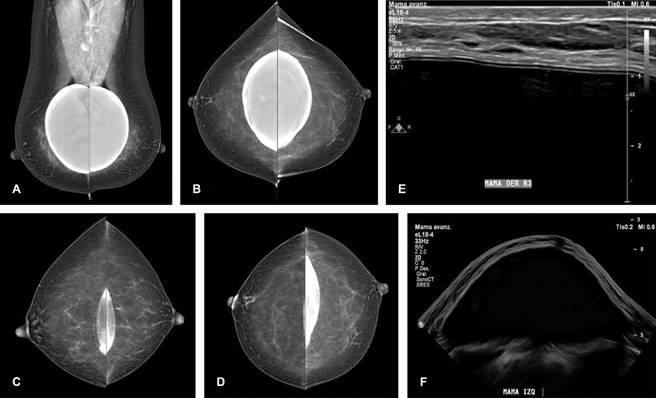

Es importante evaluar en estudios de imagen convencional las características del implante y su asociación al tiempo de colocación para contemplar las posibles complicaciones relacionadas.6 En México, los estudios de mastografía de tamizaje inician a los 40 años en pacientes con o sin implantes mamarios, en este último grupo se realizan además de las proyecciones convencionales una técnica descrita por el Dr. Eklund que consiste en desplazar el tejido mamario a medida que se comprime la mama y el implante se moviliza contra la pared torácica, logrando obtener tejido mamario para valoración del parénquima. Se requieren ocho proyecciones de mastografía que evalúan tanto los implantes como el tejido mamario: dos convencionales y dos Eklund en proyecciones cefalocaudal y medio oblicuo-lateral para cada mama (Figura 1).7 La ecografía está indicada en pacientes de cualquier edad y se deben evaluar los bordes y morfología, así como la proporción del implante con técnica panorámica o campo de visión ampliado, documentar la uniformidad del contenido y el tejido mamario circundante, sin olvidar la valoración de ganglios linfáticos axilares en el protocolo.8 En general los implantes se muestran con interior anecoico y membranas hiperecoias longitudinales, lo más común es que la envoltura externa se comporte como dos líneas paralelas ecogénicas y una línea hipoecoica entre ellas. Una técnica y equipos inadecuados podrían generar artefactos que malinterpreten los hallazgos, por lo que es imprescindible la capacitación para que el médico radiólogo pueda realizar una valoración adecuada.9

Figura 1: Valoración mastográfica y ecográfica de implantes mamarios. A) Mastografía digital bilateral en proyección convencional medio oblicuo-lateral. B) Mastografía digital bilateral en proyección convencional cefalocaudal. C) Proyecciones Eklund medio oblicuo-laterales para valoración de parénquima mamario. D) Proyecciones Eklund cefalocaudales para valoración del parénquima mamario. E) Valoración de bordes del implante por ultrasonido. F) Imagen panorámica con campo de visión ampliado para valoración del implante mamario por ultrasonido.